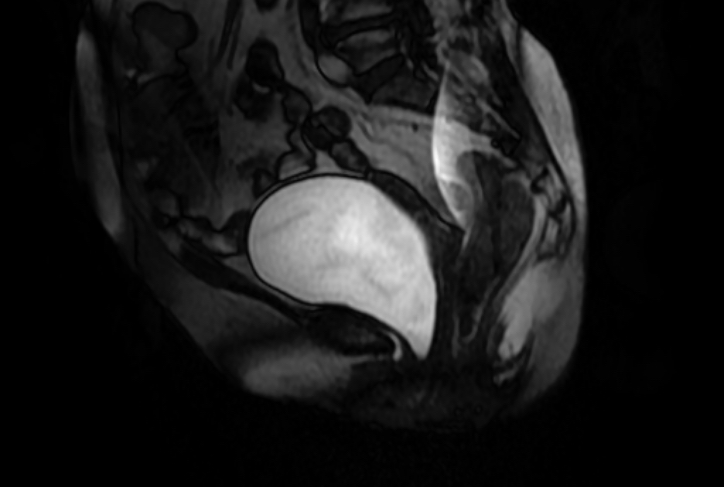

MRI diagnosis

Figure 8 MRI Sagittal image at rest

Figure 9 MRI Sagittal image on Valsalva

Preoperative Diagnosis: Vaginal anterior wall prolapse III° and vaginal posterior wall prolapse II°. Laparoscopic vaginal-presacral fixation, vaginal posterior wall repair, perineum plasty, hysterectomy plus both appendectomy were performed.

Pelvic floor ultrasound and MRI are the commonly used imaging modality in clinic. MRI has high resolution for soft tissue and high reference value for the selection of surgical methods. Yet it is expensive in examination cost and time consuming Ultrasonic examination is convenient and economical, and it is an effective method for screening and diagnosing pelvic floor dysfunction diseases.